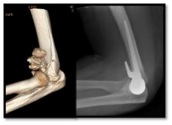

- Replacing the joint with an artificial joint- hemiarthroplasty. In an active patient who is over 65 who has a badly broken distal humerus an artificial joint is the best option. This is for nasty fractures, where the bone is thin/osteoporotic or crumbled away and reconstruction is impossible. Great results and a pain free range of movement can be achieved.